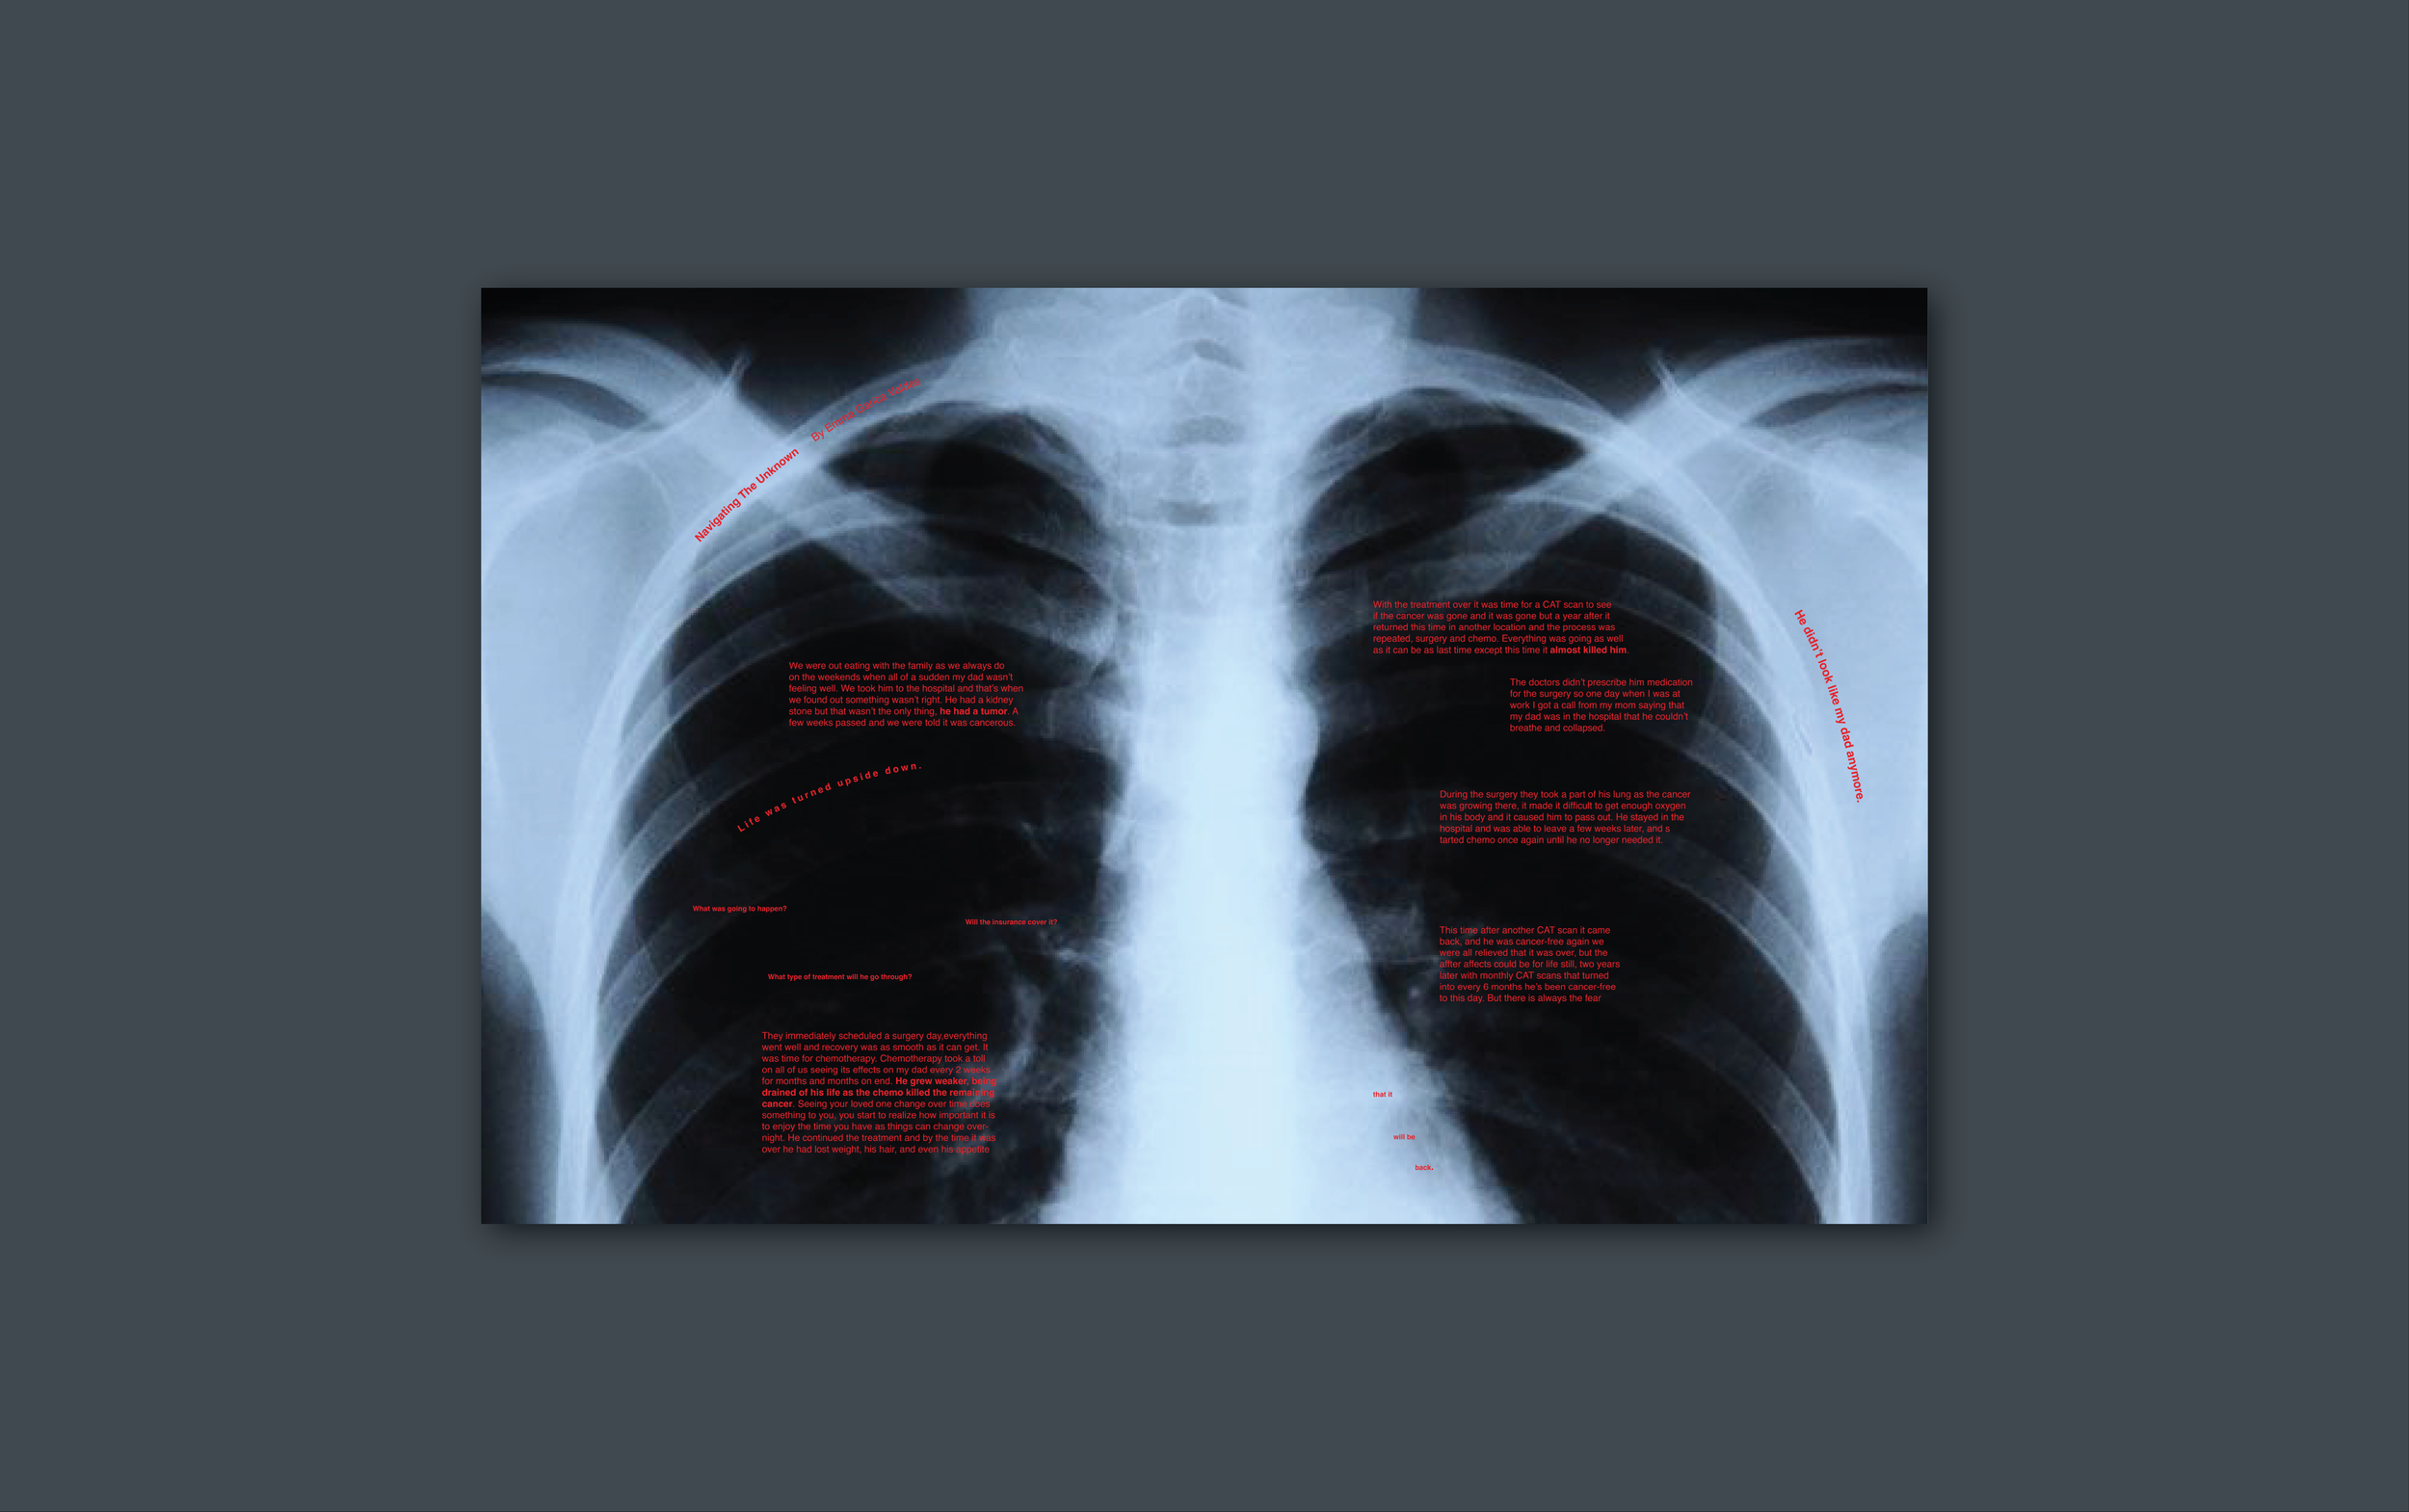

When preparing for our senior thesis, we were asked to take a story or article related to our project and explore ways to typographically translate it, using imagery, font, font size, boldness, and color while keeping the story's theme in mind.

I chose to work with a personal short story, “Navigating The Unknown,” about my dad’s cancer diagnosis and journey. I explored the ideas of growth and decay, distortion, and medical imagery, creating 4 final typographic spreads.